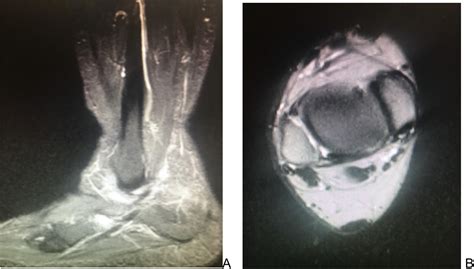

• MRI (Magnetic Resonance Imaging): This is the gold standard for visualizing soft tissue. It provides high-resolution images that clearly show tears, inflammation, or degeneration within the tendon.

• Ultrasound: A dynamic, cost-effective way to view the tendon while the foot is in motion, helping to detect subtle tears or tendon subluxation.